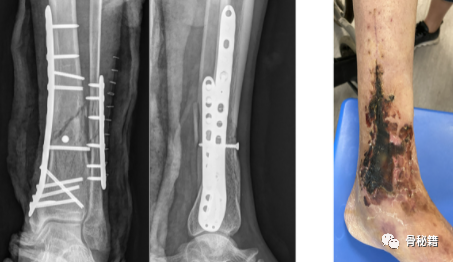

高能量损伤,不适当的切口,不合适的手术时机,不恰当的术中操作,不精细的缝合技术,不防止引流,没有放置VSD,等等等……最终导致皮肤坏死,内固定外露,伤口迁延不愈。